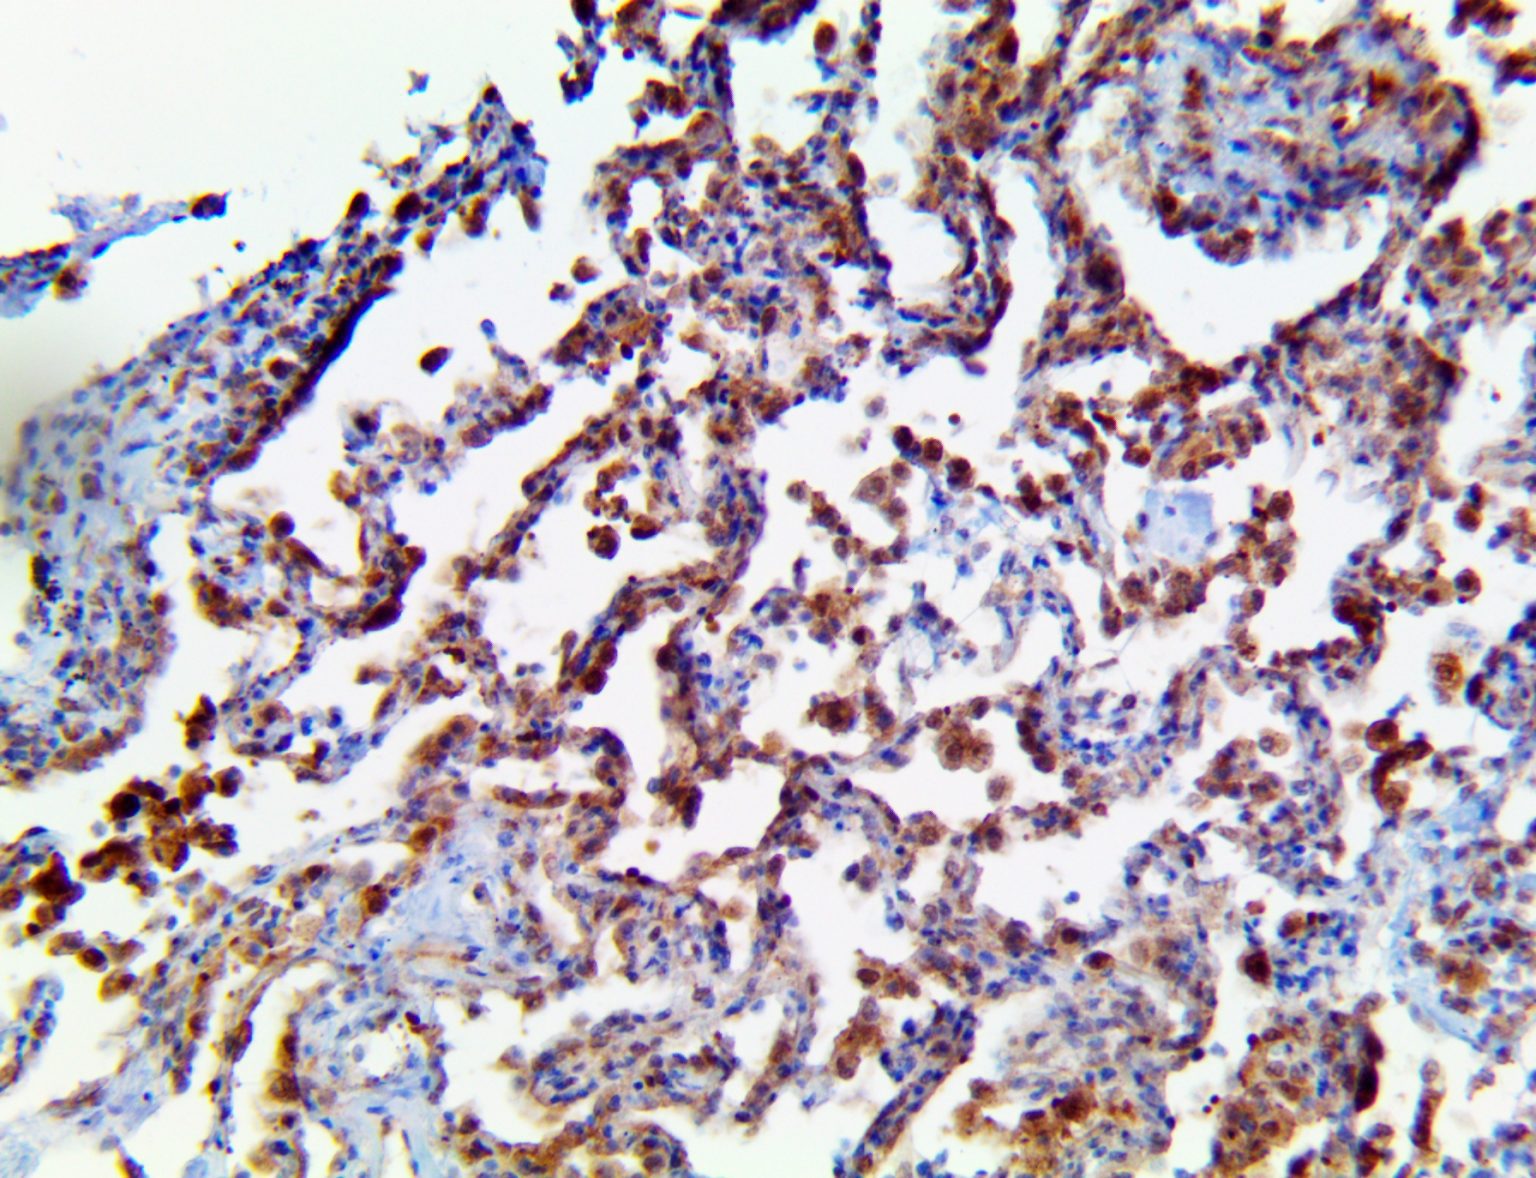

The first cytokines released are interleukin 1β (IL-1β) and tumor necrosis factor-α (TNF-α), which attract a variety of circulating white blood cells (WBCs) to the infection site, including neutrophils, monocytes, macrophages, and natural killer (NK) cells. This response, along with the antipathogenic chemicals released by these cells (i.e., complement), comprise the innate immune response. These cells directly attack the invading pathogen and also release additional cytokines, chief among them interleukin-1 and 6 (IL-6). IL-6 is essential for invoking the adaptive immune response, which calls T-cells, B-cells, and T helper (Th) cells to the infection site. IL-6 also stimulates further recruitment, proliferation and activation of macrophages.

It is the ICU physician who is most likely to witness one of the deadliest manifestations of the abnormal immunological response, the cytokine storm syndrome (CSS). This response is also referred to by some as the cytokine release syndrome (CRS). CSS is characterized by continuous activation and expansion of macrophage and lymphocyte populations, which secrete large amounts of cytokines, causing the cytokine storm. This massive cytokine release is akin to hemophagocytic lymphohistiocytosis (HLH) disease, a syndrome characterized by initial unchecked and persistent activation of cytotoxic T lymphocytes and NK cells.

This activation induces inflammatory monocytes to highly express IL-6, starting a localized and then systemic cascade effect that results in hyperproduction of IL-6, which accelerates the inflammatory process. Because IL-6 also increases vascular permeability, excessive levels cause blood vessels to become very leaky. This, along with clotting factors released from vascular endothelial cells, stimulates the coagulation cascade, resulting in microthrombosis (tiny clots), which leads to ischemia and tissue death of the kidney, intestines, heart, liver, brain and extremities.